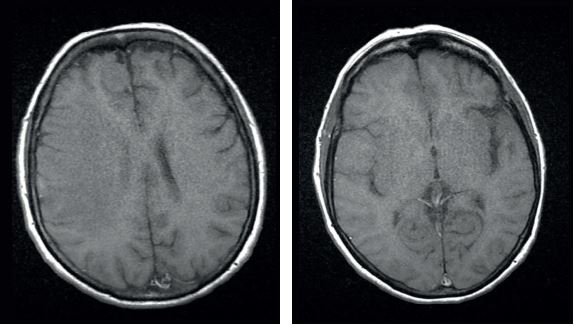

Кортикотерапія призвела до значного зменшення лімфоми та перилімфоїдного набряку.

Т1 гадоліній: Обидва ураження демонструють інтенсивне та гомогенне контрастне підсилення на Т1-зображеннях. Парафалькоріальне ураження, схоже, пов'язане з мозолистим тілом через дуральний хвіст, що вказує на екстрааксіальне ураження.